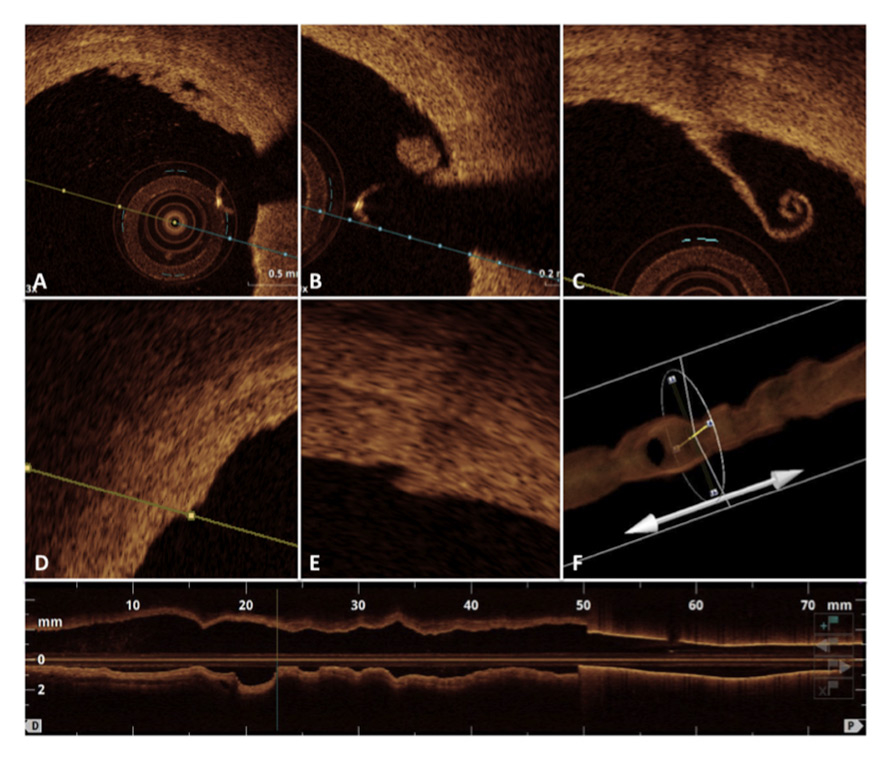

Figure 2

Intraluminal local morphological defects in the acute phase just after the procedure of renal denervation including intraluminal thrombus formations (A and B), endothelial detachment (C), vessel wall oedema (D), dissection (E) and massive vascular vasospasm as detected by the 3D optical coherence tomography reconstruction.

The OCT pullbacks performed before and after each procedure documented in total 141 different local acute morphological vascular changes. In detail, 60 areas of prominent oedema, 57 intraluminal thrombi, 21 vessel vasospasms and 3 wall dissections were observed (fig. 2). The total amount of all vascular lesions including the combination of oedema, thrombus formation, dissections and spasms did not reveal any correlation to BP reduction at 1, 3 and 6 months follow-up (office BP and 24-h ABPM) (fig. 3). Furthermore, no correlation between oedema and BP reduction was documented at any time of follow-up (fig. 4).